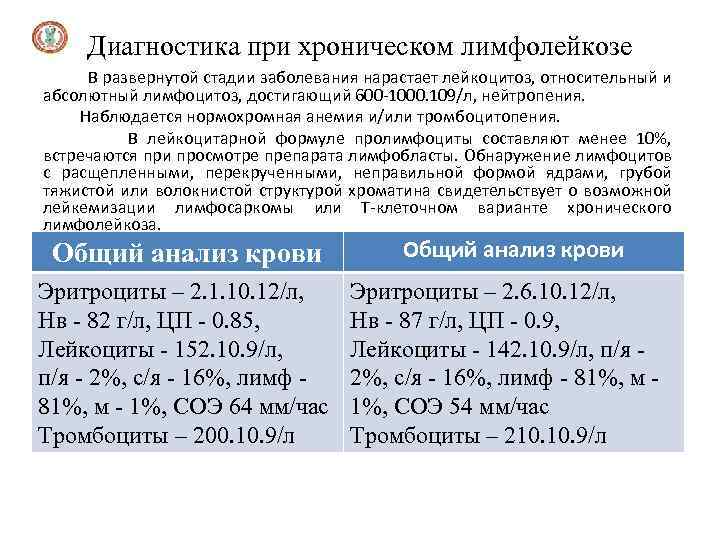

Диагностика при хроническом лимфолейкозе В развернутой стадии заболевания нарастает лейкоцитоз, относительный и абсолютный лимфоцитоз, достигающий 600 -1000. 109/л, нейтропения. Наблюдается нормохромная анемия и/или тромбоцитопения. В лейкоцитарной формуле пролимфоциты составляют менее 10%, встречаются при просмотре препарата лимфобласты. Обнаружение лимфоцитов с расщепленными, перекрученными, неправильной формой ядрами, грубой тяжистой или волокнистой структурой хроматина свидетельствует о возможной лейкемизации лимфосаркомы или Т-клеточном варианте хронического лимфолейкоза. В периферической крови могут обнаруживаться единичные крови Общий анализ миелоциты и Общий анализ крови инфекционных заболеваний, а также метамиелоциты, обычно на фоне нормобласты Эритроциты – 2. 1. 10. 12/л, Нв - 82 г/л, ЦП - 0. 85, Лейкоциты - 152. 10. 9/л, п/я - 2%, с/я - 16%, лимф - 81%, м - 1%, СОЭ 64 мм/час Тромбоциты – 200. 10. 9/л Эритроциты – 2. 6. 10. 12/л, Нв - 87 г/л, ЦП - 0. 9, Лейкоциты - 142. 10. 9/л, п/я - 2%, с/я - 16%, лимф - 81%, м - 1%, СОЭ 54 мм/час Тромбоциты – 210. 9/л